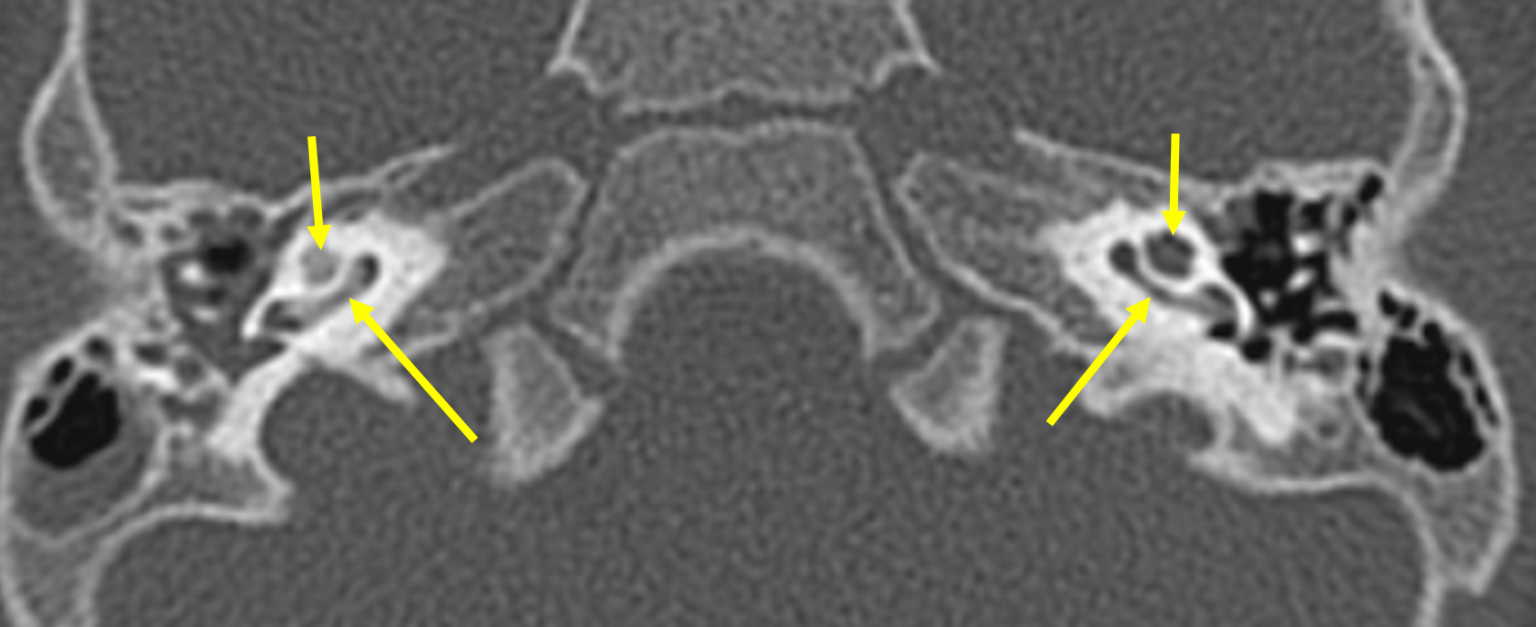

Neuroradiology On the Net Labyrinthitis ossificans Labyrinthitis Web labyrinthitis is an inflammation of the membranous labyrinth of the inner ear and typically presents with vertigo, nausea, vomiting, tinnitus,. Web learn about the symptoms, causes and treatment of inner ear infections that affect your balance. Web labyrinthitis is a balance disorder caused by an infection or inflammation of the inner ear. Learn about the types, risk factors, diagnosis,. Labyrinthitis.

Labyrinthitis ossificans Radiology Cases Labyrinthitis Web labyrinthitis is an inner ear infection that can affect balance and hearing. Find out when to see a gp,. Web labyrinthitis is a balance disorder caused by an infection or inflammation of the inner ear. Web labyrinthitis is a condition that causes inflammation in the inner ear and affects your balance and hearing. Web labyrinthitis is an inflammation of. Labyrinthitis.